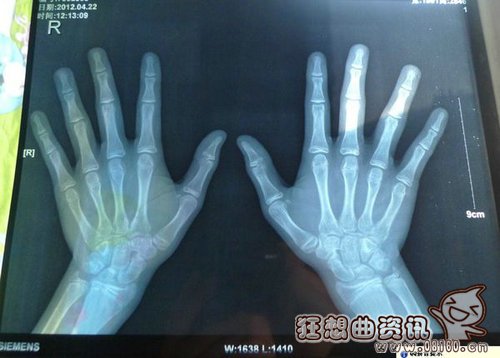

骨骼:骨头变得粗大,皮下脂肪层更加结实,这可以防止摔倒时骨折;